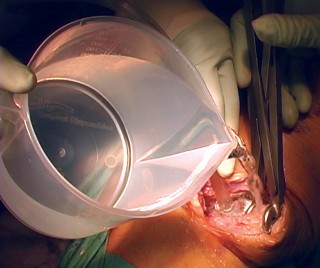

استبدال مفصل الركبة بالإسمنت: تفاصيل العملية

تُعد عملية استبدال مفصل الركبة بالإسمنت إجراءً دقيقًا يتطلب مهارة وخبرة عالية، وهو ما يوفره الأستاذ الدكتور محمد هطيف لمرضاه في صنعاء. تهدف العملية إلى إزالة الأسطح المفصلية التالفة واستبدالها بمكونات اصطناعية (غرسات) تُثبت في مكانها باستخدام إسمنت عظمي خاص.

التحضير للعملية

خطوات العملية الجراحية بالتفصيل